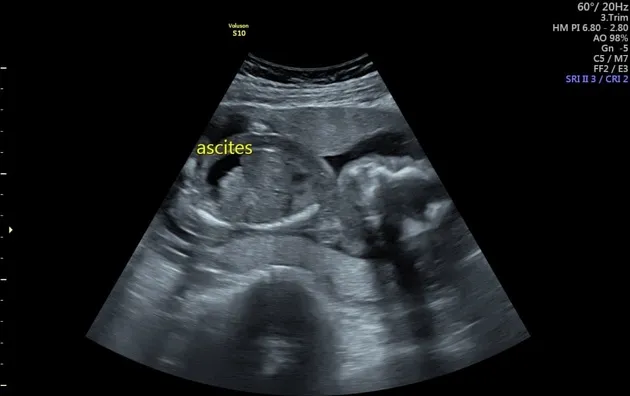

- Parvovirus B19: Can cause severe fetal anemia, leading to hydrops fetalis (fetal CHF).

- Maternal Parvovirus B19 can cause fetal hydrops fetalis.